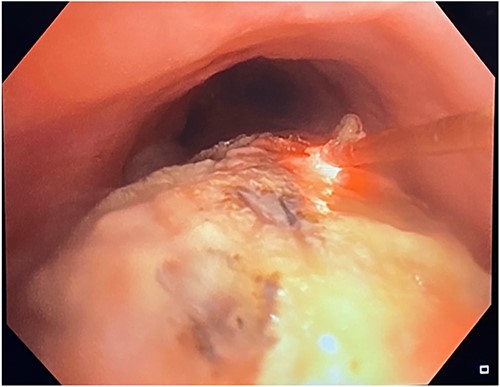

In April of 2022, the patient developed recurrent pneumonias, hemoptysis, and progressive dyspnea, raising concern of tumor invasion into the airway. Bronchoscopy confirmed a large tumor encompassing 2/3 of the airway, with evidence of stent erosion through the trachea (August 2022, Fig. 3). Laser debridement of the tumor was successfully performed.

Bronchoscopic evidence of tumor growth into the trachea with evidence of stent erosion (August 2022).

This was the first clear evidence of esophagotracheal communication. Laser debridement was successfully performed again in November 2022, leaving only a small portion where the stent eroded the trachea. On post-bronchoscopy Day 3, the patient reported significant improvements in breathing and energy. Over 6 months, she underwent laser debulking of the tracheal mass twice to manage tumor ingrowth (January and April 2023). Debridement was performed each time using a neodymium-yttrium-aluminum-garnet laser (Fig. 4). Between 380 and 560 joules were delivered to cauterize and debulk the invading tumor. The patient continues to be followed for palliative tumor debulking for ongoing symptom management.

Bronchoscopic view of the endobronchial obstruction. Invasion of the esophageal malignancy can be seen, as well as erosion of the esophageal stent into the lumen of the trachea.